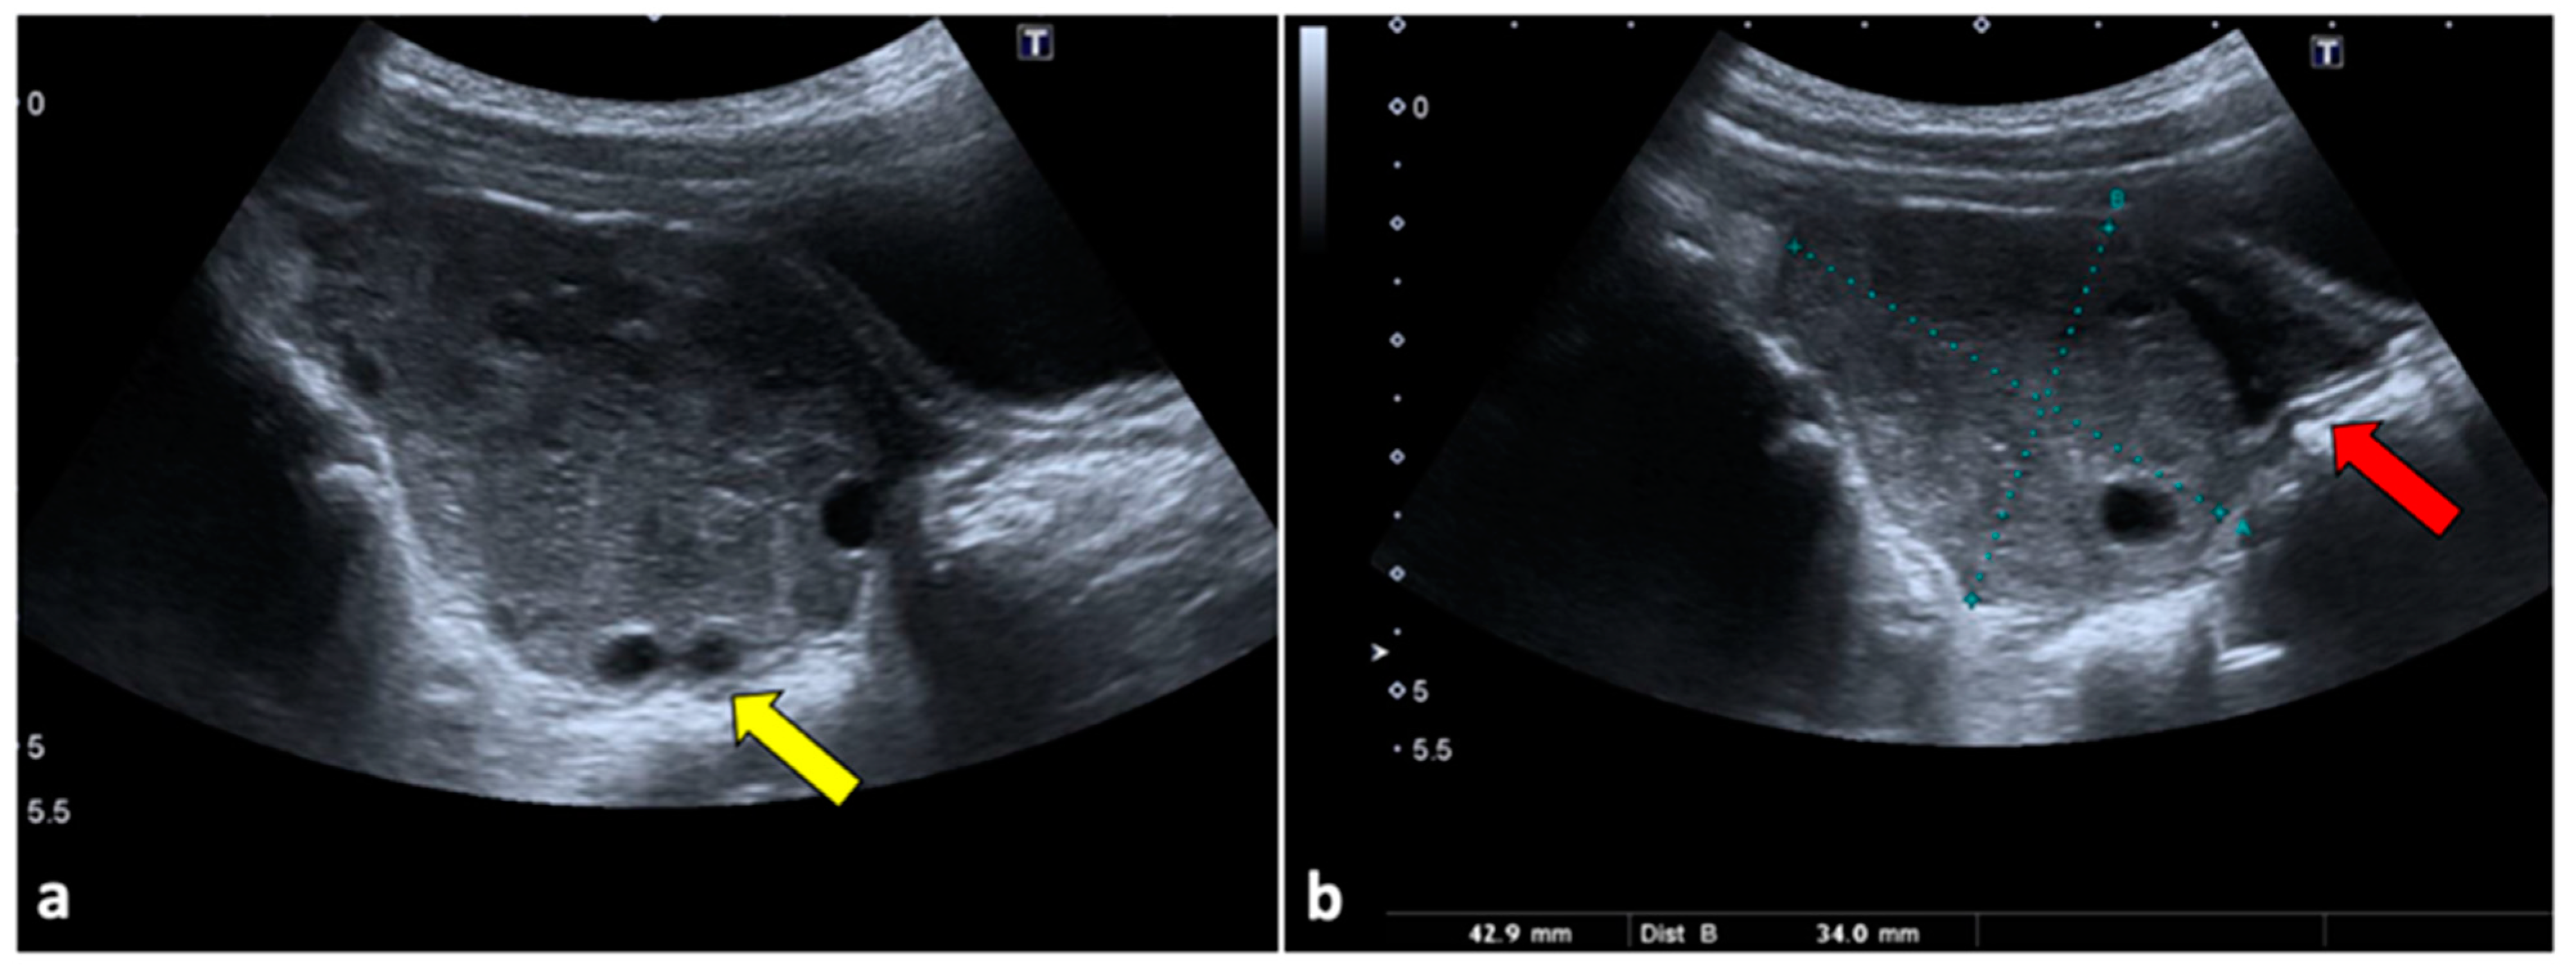

2.1. Ovarian Torsion

2.2. Ovarian Cyst Haemorrhage/Rupture